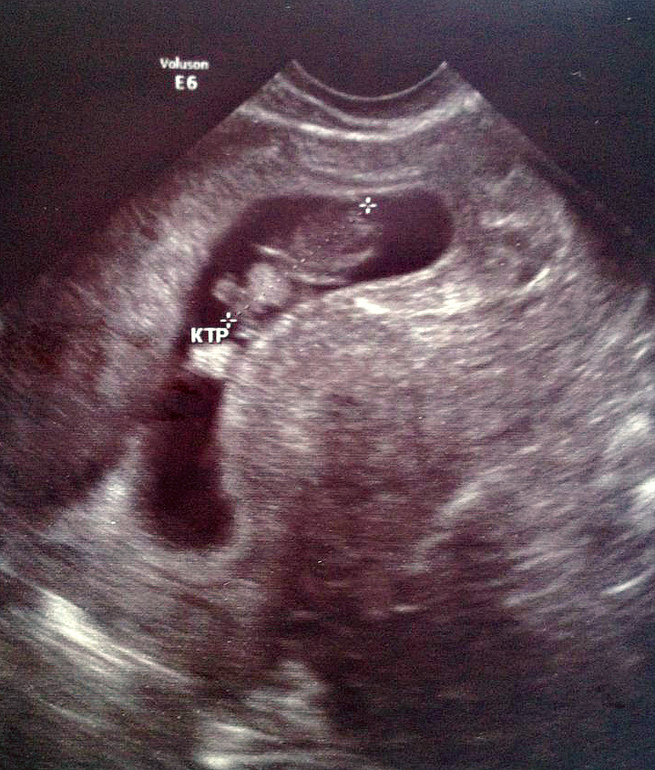

Услышала я своего малышика наконец то, а нам ведь 9 недель завтра! По размеру мы тянем на 8,4. КТР 19,6 мм. ЧСС 182 уд\мин...

Про тонус ничего врач не сказал и не написал.... Но как я поняла, у меня как и в прошлую неудачную беременность, малыш прикрепился низко. ПОЧЕМУ?

Дословно в бумажке подчеркнуты слова: Приемущественная локализация хориона ЗАДНЯЯ , ОБЛАСТЬ ВНУТРЕННЕГО ЗЕВА((

я принимаю 6таблетой в день утрика....не могли бы вы еще прокомментировать фото? врач говорит что яйцо такое изза того что узист под таким углом посмотрел. и про тонус не говорил узист.... но ведь яйцо плохое?

Я не вижу "плохого" яйца!Если Вы имеете в виду темную полость неровных очертаний,то это полость матки!Откуда информация про тонус у Вас?)

ну на фотографиях я смотрю у девочек в календаре беременности, оно у большинства круглое, а у меня сарделька)

Это не яйцо))))Это внутренняя полость матки в разрезе как бы)))И зависит от положения датчика на момент съемки)

Это тело матки.А "сарделька"Ваша-это полость ее)))Оболочку не видно здесь)